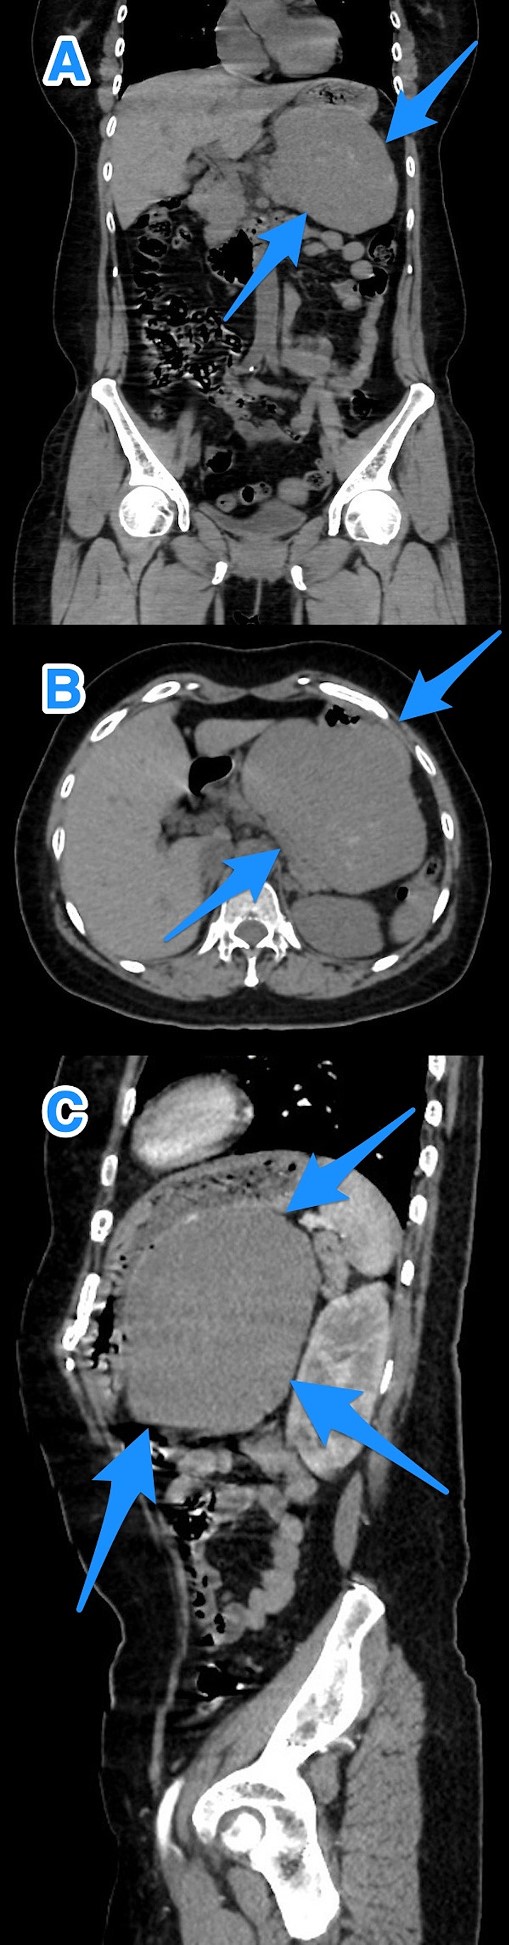

Upon clinical examination, the patient was alert but pale and dehydrated, with a heart rate of 125 bpm, blood pressure of 100/54 mmHg, and melena noted on rectal examination. Laboratory tests showed a leukocyte count of 13.8 x 109/L, a hemoglobin level of 5.8 g/dL, and a hematocrit level of 16.8%. After resuscitation, an ultrasound showed a large hypoechoic lesion near the left liver lobe and behind the pylorus. A computed tomography (CT) scan revealed a large, well-defined mass (12.6 x 8 x 12.7 cm) in the gastric fundus/body, touching liver segment III and positioned between the stomach and pancreas, affecting the left gastric artery branches (Fig. 1).

A multi-view computed tomography scan of the abdomen (A–C) showing a well-defined large gastric fundal/body submucosal heterogeneously hypoenhancing soft tissue mass lesion of the posterior gastric wall (arrows).